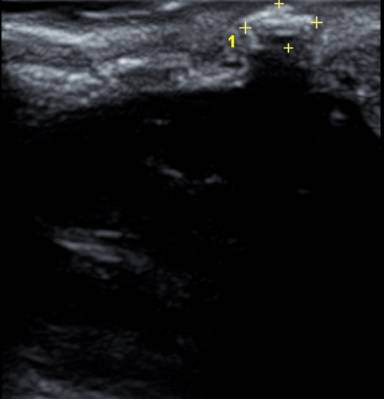

▲타석증의 초음파 소견

음식을 먹을 때 턱밑이 부어오르거나 혀 밑이 부어오르고 통증을 느낀다면 타석증을 의심해야 합니다. 타석증이란 침샘에서 침이 분비되어 나오는 침샘관에 돌이 생기는 질환입니다. 침이 나와야 하는 길목을 돌이 막고 있기 때문에 침샘내에 침이 정체되어 분비가 안되어 침샘 부위가 붓고 염증이 생깁니다. 대개 침샘염을 유발하는 가장 흔한 원인으로 타석증을 들 수 있습니다.

정확한 원인은 알 수 없지만 침의 분비가 정체되고, 침샘관 내의 상피의 염증 등으로 인해 침 성분에 포함되어 있는 칼슘염의 침착으로 발생합니다. 대부분의 타석증은 턱밑샘(80%)에 생기고 귀밑샘(19%)이나 다른 침샘(1-2%)에 생기는 경우는 비교적 드뭅니다.

대개 식사 후에 턱밑이 부어오르면서 통증이 반복적으로 생기고 심한 경우에는 침샘관으로 농이 배출되는 경우도 있습니다. 이러한 반복되는 침샘염으로 침샘이 위축되고 침샘관이 협착을 초래하여 만성 침샘염을 유발하기도 합니다.